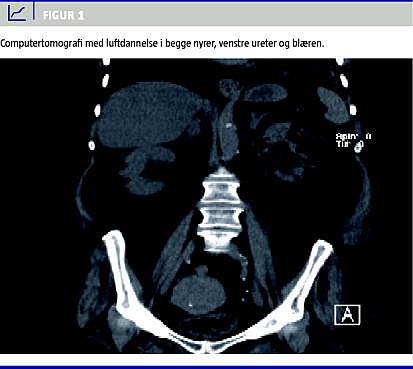

Hun havde ved indlæggelsen fire dages anamnese med abdominalsmerter og febrilia samt mikroskopisk hæmaturi, pyuri og akut nyreinsufficiens. Få timer efter indlæggelsen faldt blodtrykket til 68/38. Shocktilstanden udløste en akut computertomografi (CT) af abdomen, som viste luftdannelse i parenkymet i begge nyrer, venstre ureter og blæren (Figur 1 ). Der fandtes plasmakreatinin på 268 mikromol /l, metabolisk acidose og tegn på svær infektion (C-reaktivt protein (CRP): 270 mg/l og trombocytopeni 108 mia/l).

Summary Renal and urethral gas production as a complication to infection of the urinary tract Ugeskr L&aelig;ger 2010;172(35):2389-2390 Emphysematous pyelonephritis (EPN) is a bacterial infection characterised by gas production in the renal parenchyma. We present a case with EPN caused by Klebsiella pneumoniae sepsis. The 74-year-old woman was admitted in septic shock. An acute computed tomography revealed gas bubbles bilaterally in the renal parenchyma, left urethra and bladder. Treatment consisted of three types of antibiotics and intravenous fluids. She was discharged two months later without need for surgical treatment or haemodialysis despite the seriousness of her initial condition.